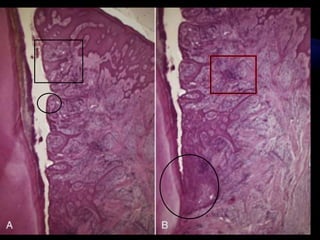

HISTOPATHOLOGIC

FEATURES

Gingival wall of pocket presents

• Bluish red discoloration;

•Flaccidity;

• Smooth, shiny surface; & pitting on pressure

Discoloration  circulatory stagnation

flaccidity destruction of gingival fibers

Smooth shiny surface, pitting on pressure 

Edema atrophy of epithelium degeneration

Less frequently

Gingival wall may be pink and firm.

Fibrotic changes predominate over exudation

and degeneration (external wall)

Bleeding on probing Vascularity thinning , degeneration of

epithelium , proximity of engorged vessels to

inner surface.

When explored inner wall of pocket is painful Pain on tactile stimulation is caused by

ulceration of inner aspect of pocket wall

Pus may be expressed by applying digital

pressure

Suppurative inflammation of inner wall

1. Changes in the soft tissue wall

a. Blood vessels are increased in number , dilated and enlarged

b. Connective tissue is edematous and densely infiltrated with

plasma cells (80%) , lymphocytes , scattering of PMN’s .

c. JE becomes shorter

d. Degeneration and necrosis of the epithelium leading to

ulceration of the epithelium and exposure of the underlying

connective tissue.

 Proliferation of endothelial cells capillaries

fibroblast collagen fibers

 Bacterial invasion along the lateral and apical

areas of the pocket.

 Areas of quiescence

 Areas of bacterial accumulation

 Areas of emergence of leukocytes

 Areas of leukocyte-bacteria interaction

 Areas of intense epithelial desquamation

 Areas of ulceration

 Areas of hemorrhage